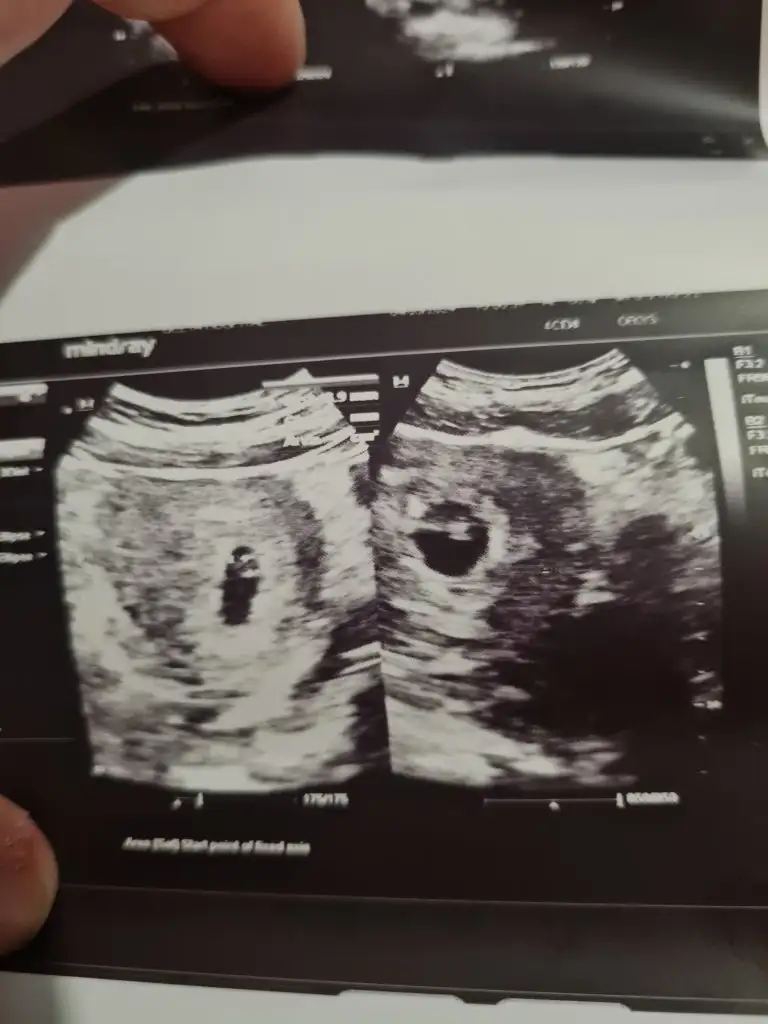

Merhaba sizinkini tam anlayamadım çok farklı acilar hepsi .. vajinal mı bakıldı karından mı? Yardımcı olmaya çalışıyorum ama tam anlayamadım.Saglikla kucağınıza almak nasip olsunMerhaba arkadaslar 7 haftalık gebeyimEki Görüntüle 3398802 Eki Görüntüle 3398801

Bende zaten pek anlayamadım her açıdan çekmiş doktorMerhaba sizinkini tam anlayamadım çok farklı acilar hepsi .. vajinal mı bakıldı karından mı? Yardımcı olmaya çalışıyorum ama tam anlayamadım.Saglikla kucağınıza almak nasip olsun

Bu arada karından baktıMerhaba sizinkini tam anlayamadım çok farklı acilar hepsi .. vajinal mı bakıldı karından mı? Yardımcı olmaya çalışıyorum ama tam anlayamadım.Saglikla kucağınıza almak nasip olsun

Canım benimkini de yorumlar mısınız hepsi karından 1. 6+4haftalık 2. 8+5 haftalık 3. 10 haftalık 4. 11+5 haftalıkAllah sağ salim kucağınıza almayı nasip etsin inşallahvajinal ultrason mu öyleyse kız bence